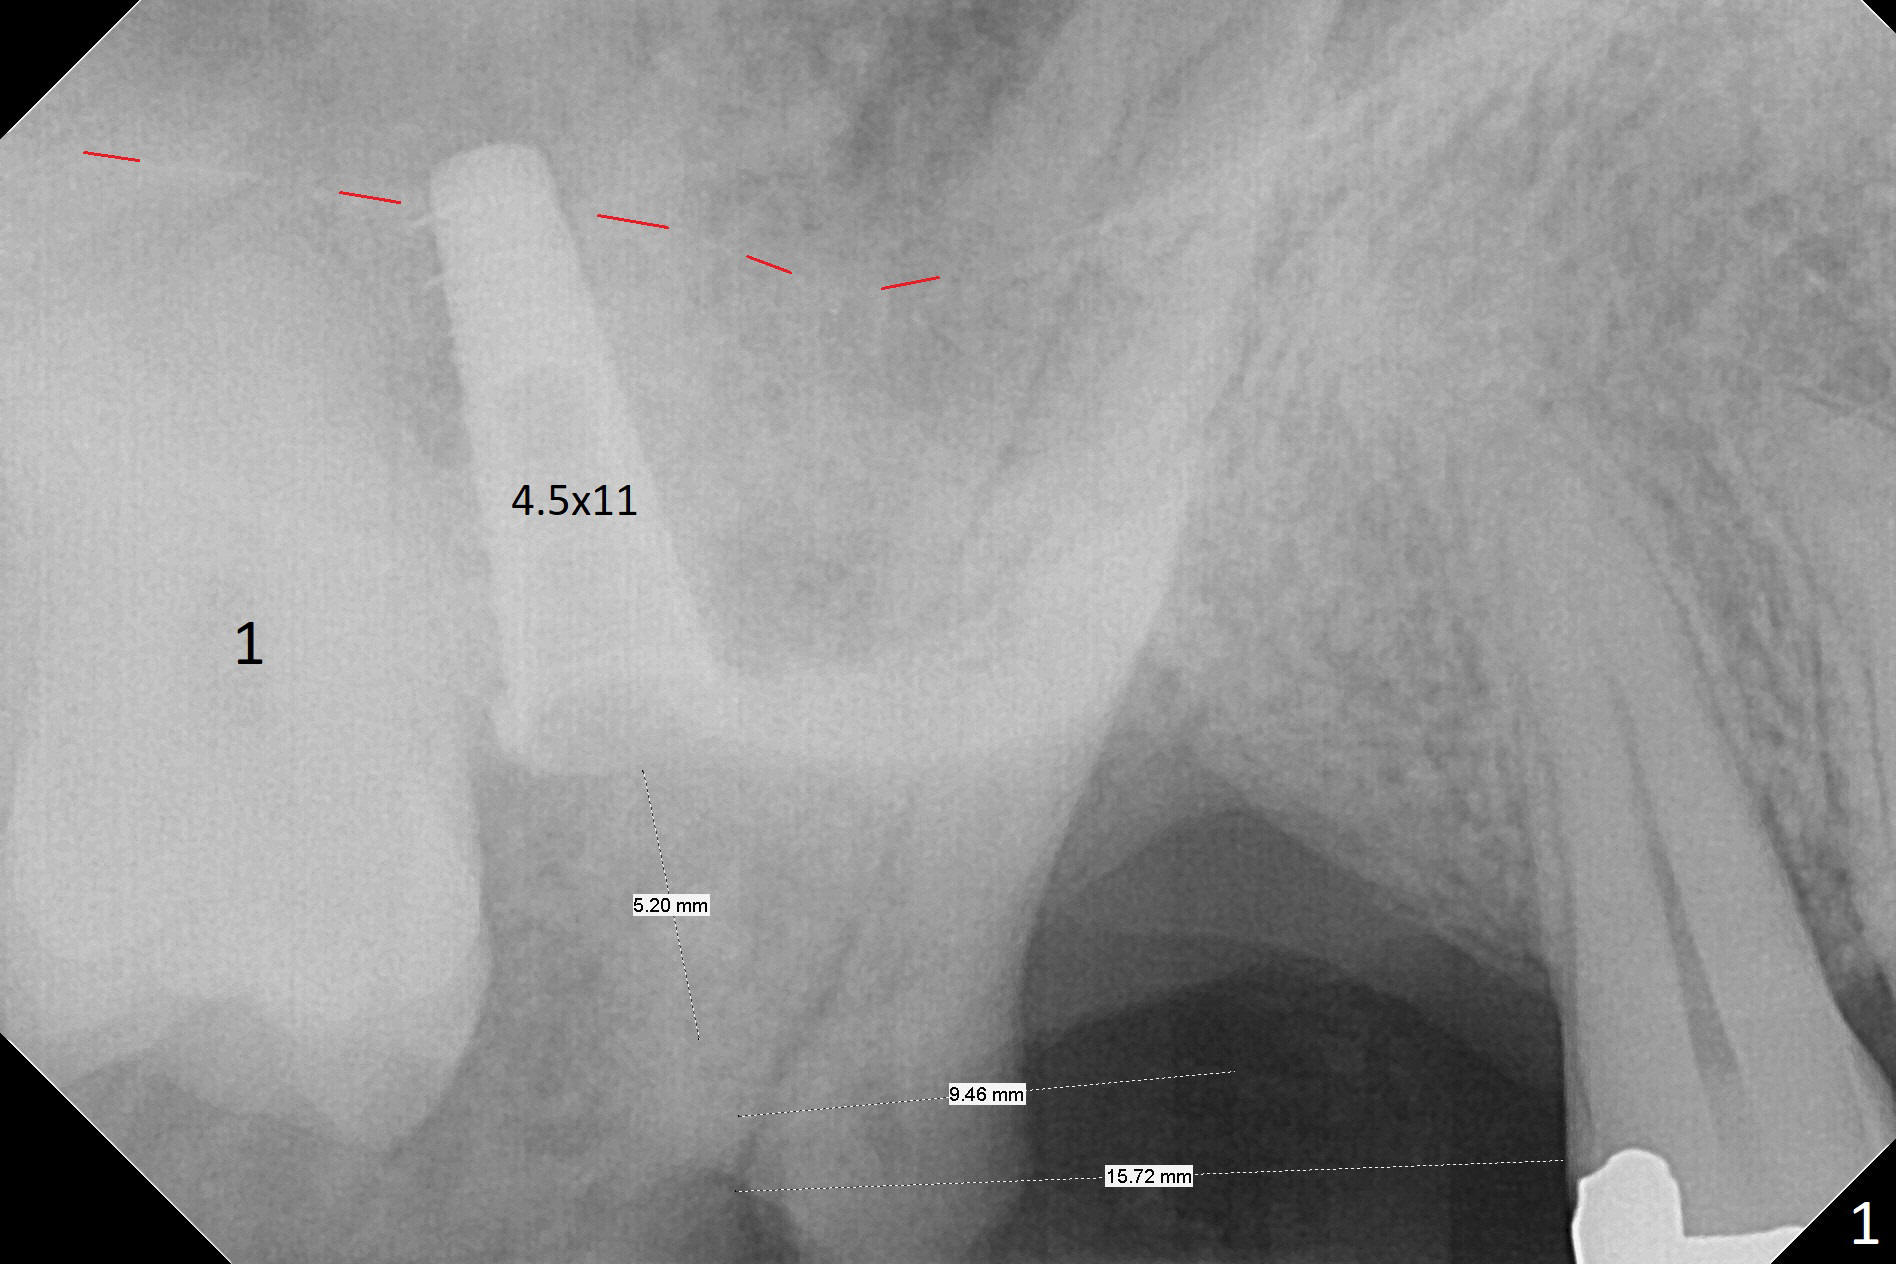

It is difficult to use hard tissue landmark (drill stopper) to make osteotomy in the fresh extraction socket because of socket irregularity and hemorrhage. Once osteotomy is initiated, depth is more reliably controlled with soft tissue landmark (such as gingival margin). This happens in today's case. Without CT information, the osteotomy is established in the buccal slope of the septum of the tooth #2 (after extraction) by using alternatively Magic Sinus Lifter and 4.8 mm Magic Drill (MD). Finally the sinus floor (Fig.1 red dashed line) is lifted after the MD reaches ~16 mm counting from the gingival margin, consistent with preop panoramic X-ray and intraop PA measurement. The 4.5x11 mm dummy implant is close to the impacted 3rd molar (1). Following use of Lindamann bur to move the osteotomy mesially, a 5x9 mm dummy implant is placed away from the 3rd molar (Fig.2 (3: residual root of the 1st molar)). The latter is intentionally not removed in order to maintain osteotomy integrity. A 5x13 mm IBS implant is placed with >50 Ncm; a 6.5x4(4) mm abutment is hand tightened (Fig.3). The remaining large socket is filled with Vera Graft (Fig.4 *). Two months postop, the abutment changes to 6.5x5.7(2) mm without provisional (Fig.5). Nearly 3 months postop, the patient will return for #3 residual root extraction and implant placement with incision (Fig.6). Osteotomy will be initiated in a slope. Prepare surgical round bur for flattening. After placement of a healing abutment, periodontal dressing is to be applied. Take photos to show gingival adaptation to the new abutment without implant exposure at #2.